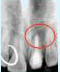

X-ray showing

picture line

Tooth with Fracture Extending Sub-Gingivally